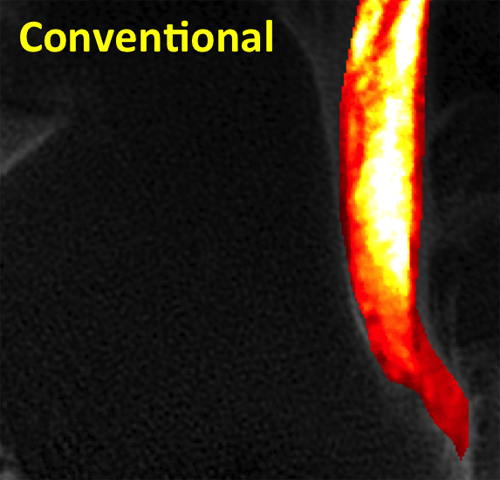

Tendon Quantitative

Quantitative MRI reveals marked changes in T2 values with bright signal centrally representing collagen fiber disorganization.